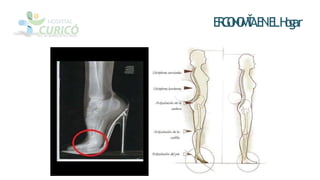

La ergonomía se encarga del diseño de lugares de trabajo y tareas para que coincidan con las características fisiológicas y capacidades de los trabajadores. Esto incluye promover posturas saludables para prevenir lesiones en la columna vertebral y factores de riesgo. Algunas recomendaciones son realizar pausas saludables, levantar objetos correctamente y evitar mantener la cabeza encorvada por mucho tiempo.